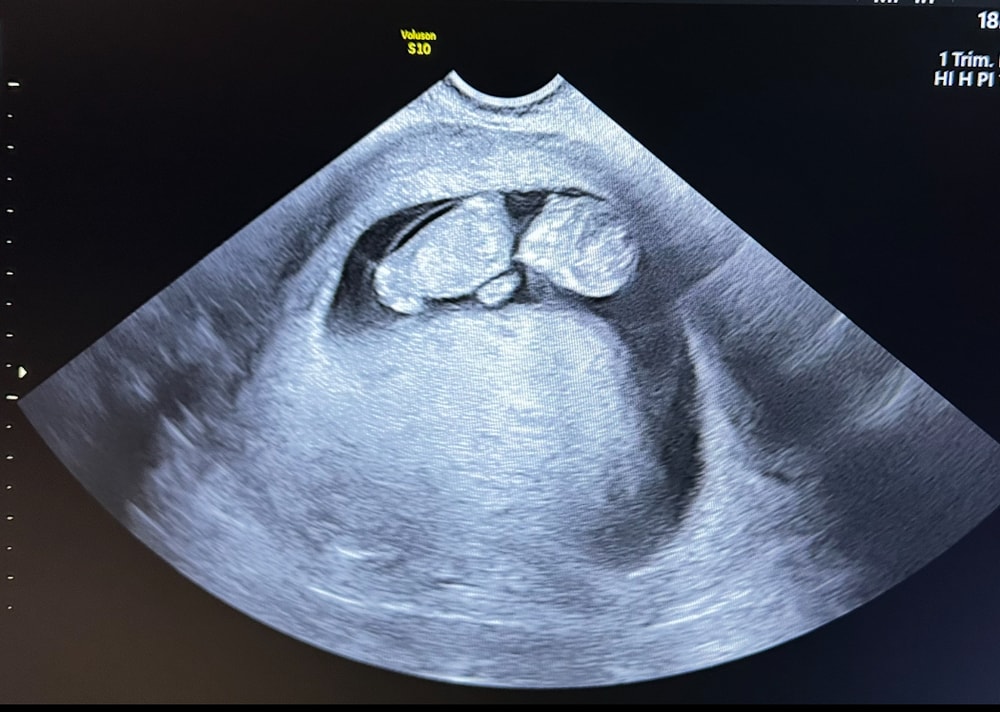

малышка выросла за 2 недели на 350гр ❤️ ее мать похудела на 200гр😅

предположительная масса плода 2400. Врач сказала , что к 37-38н будет 3300 примерно 😄 ну вот это я понимаю , так и рожала своих девочек на этом сроке 🤗 младшая дочь уже вся извелась 🤣ждет сестру , аж в пупок кричит - скоро май !!!! Слышишь ???!!!😅